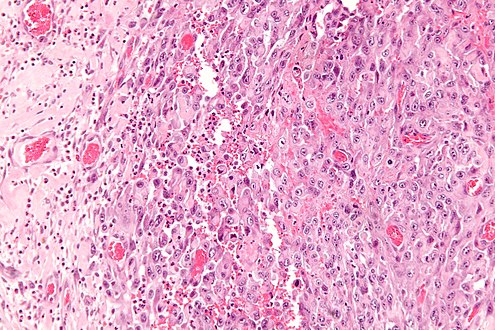

| Micrograph of an epithelioid sarcoma. H&E stain. | |

Histologically, epithelioid sarcoma forms nodules with central necrosis surrounded by bland, polygonal cells with eosinophilic cytoplasm and peripheral spindling.[3] Epithelioid sarcomas typically express vimentin, cytokeratins, epithelial membrane antigen, and CD34, whereas they are usually negative for S100, desmin, and FLI1 (FLI-1).[3] They typically stain positive for CA125.[4]

The most common genetic mutation (found in 80-90% of epithelioid sarcomas) is the inactivation of the SMARCB1 gene, or the loss of INI-1 function,[10][11] which is thought to be a major contributor to disease progression. Epithelioid sarcoma typically contains chromosome 22q11.2 mutations or deletions and 8q gains, particularly i(8) (>q10). Aberrations of 18q and 8q, as well as recurrent gains at 11q13, have also been observed.[12][13][14]

Tissue biopsy is the diagnostic modality of choice. Due to a high incidence of lymph node involvement, a sentinel lymph node biopsy is often performed. A common characteristic of epithelioid sarcoma (observed in 80% of all cases) is the loss of function of the SMARCB1 gene (also termed BAF47, INI1, or hSNF5). Immunohistochemical staining of INI1 is available and can be used for the diagnosis of epithelioid sarcoma. MRI is the diagnostic modality of choice for imaging prior to biopsy and pathologic diagnosis, with the primary role being the determination of anatomic boundaries.[citation needed]

High mag. (SMARCB1)